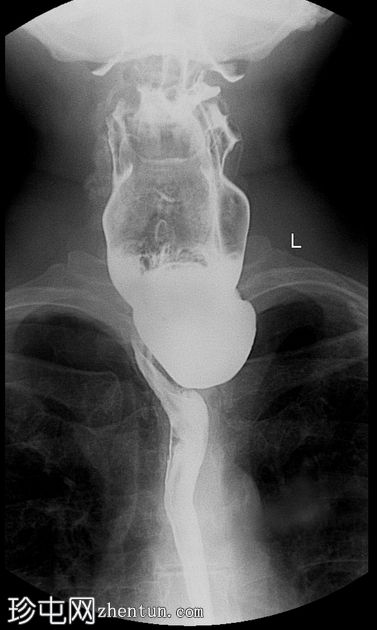

钡餐检查

3.jpeg

正位

可见一充满造影剂的、向后突出的憩室,位于咽食管交界处后壁,大致在T1椎体水平。憩室颈部狭窄,与颈段食管相通。吞咽时憩室充满造影剂,延迟显像显示造影剂滞留。食管其余部分管径和走行正常。未见远端梗阻。

表现为后正中线向外突出的囊状物,颈部狭窄,位于 T1(C5-C6)水平或略低于该水平。